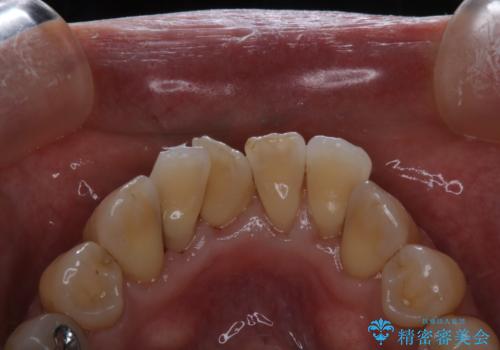

- これから、全体的な総合治療がスタートするため、着色や汚れをきれいにしてほしいとのことでした。PMTC60分コースを行いました。

施術後の歯の表面に、茶色く色が残っている所がありますが、これは詰め物の変色の所と、虫歯になっている所です。以前に、CR(コンポジットレジン)による虫歯治療がされています。

CRは経年的劣化や、着色してしまうことがあります。PMTCでクリーニングを行うと、古いCRが目立つことがあるため、気になる際は詰め替えを行います。

茶色くなっている部分が、着色なのか、劣化なのか、虫歯によるものなのかは判別が難しいことがあります。そのため、定期的にPMTCを行うことで状態の確認が的確に行えます。